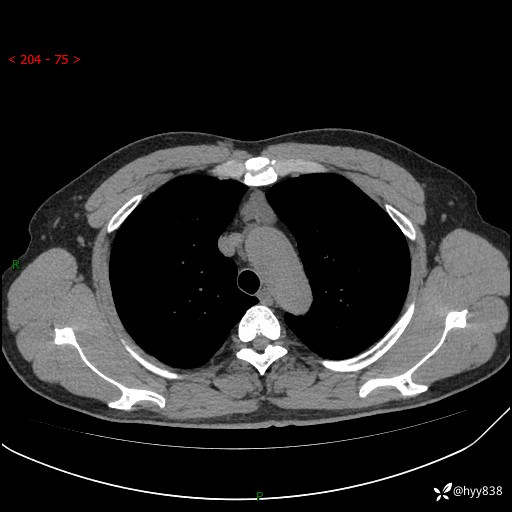

患者性别:女

患者年龄:49岁

简要病史:跟骨骨折,常规CT发现纵隔占位

辅助检查:CT

临床诊断:纵隔占位

胸部CT平扫